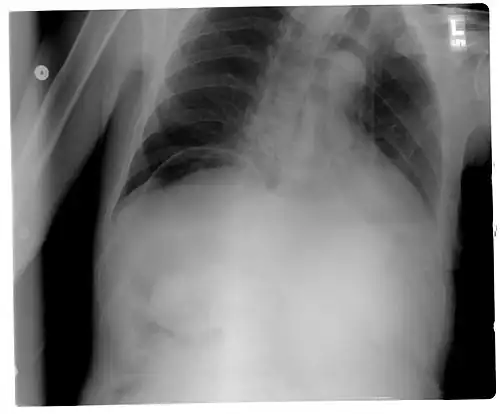

Signs that can be seen on projectional radiography are shown below:

Another pneumoperitoneum on chest X-ray. -